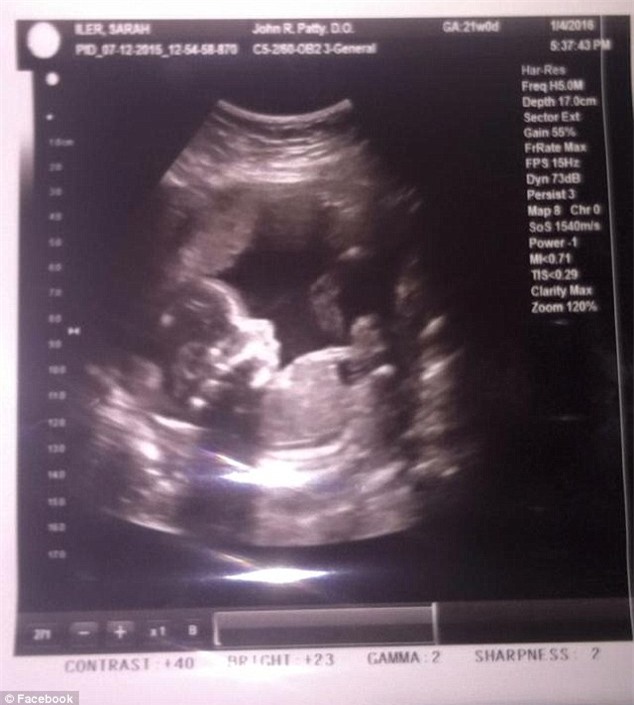

Hình ảnh em bé khi còn trong bụng mẹ.

Trước đó, cô Sarah rất hạnh phúc khi chuẩn bị chào đón đứa con đầu đời của mình.